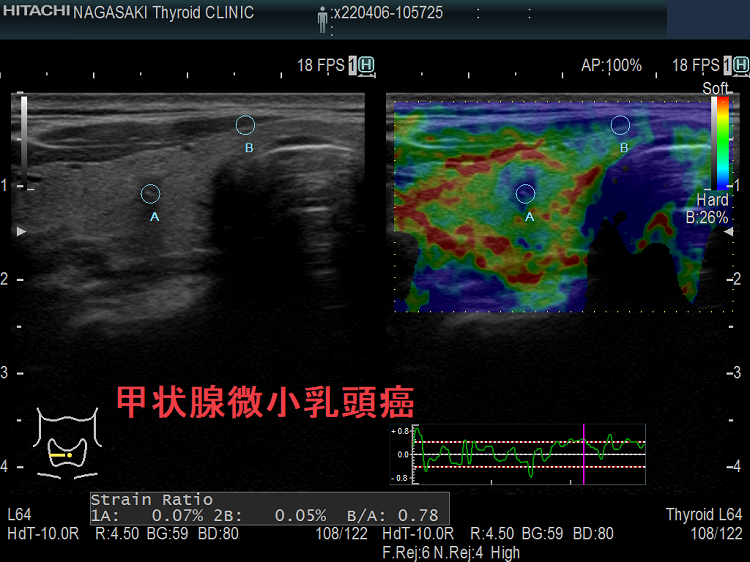

甲状腺微小乳頭癌は超音波エコー検査でどう見えるか①極めて低エコー(不整形、境界不明瞭、辺縁粗雑)で橋本病(慢性甲状腺炎)の破壊による変性と鑑別難②環状高エコー被膜③石灰化(微細石灰化・斑点状・卵殻状石灰化は通常型と同じ、破片状・塊状石灰化が多い)。甲状腺微小乳頭癌で反回神経浸潤(Ex1,Ex2)が術前・術中に見つかるのは、腫瘍が背側かつ気管寄りの場合。甲状腺超音波(エコー)では腺腫様結節にしか見えず、エラストグラフィーで軟らかく、10mmに満たないが穿刺細胞診すると甲状腺微小乳頭癌の事がある。女性の30人に1人の割合で甲状腺乳頭癌が存在。

しかし、長年、甲状腺超音波(エコー)検査を行ってきた筆者の経験では、そこまで多くないと感じていました。ところがギッチョン、思わぬ落とし穴が・・・。甲状腺超音波(エコー)上、どう見ても腺腫様結節で甲状腺微小乳頭癌とは思えないものがあります。エラストグラフィーでも軟らかく、細胞診をする必要性も感じません。それが、まさかの甲状腺微小乳頭癌だったのです。

ケース①